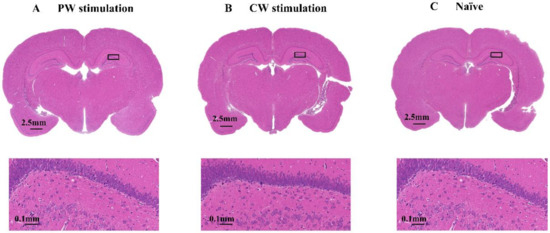

3.4. Histological Examination of Brain Injuries